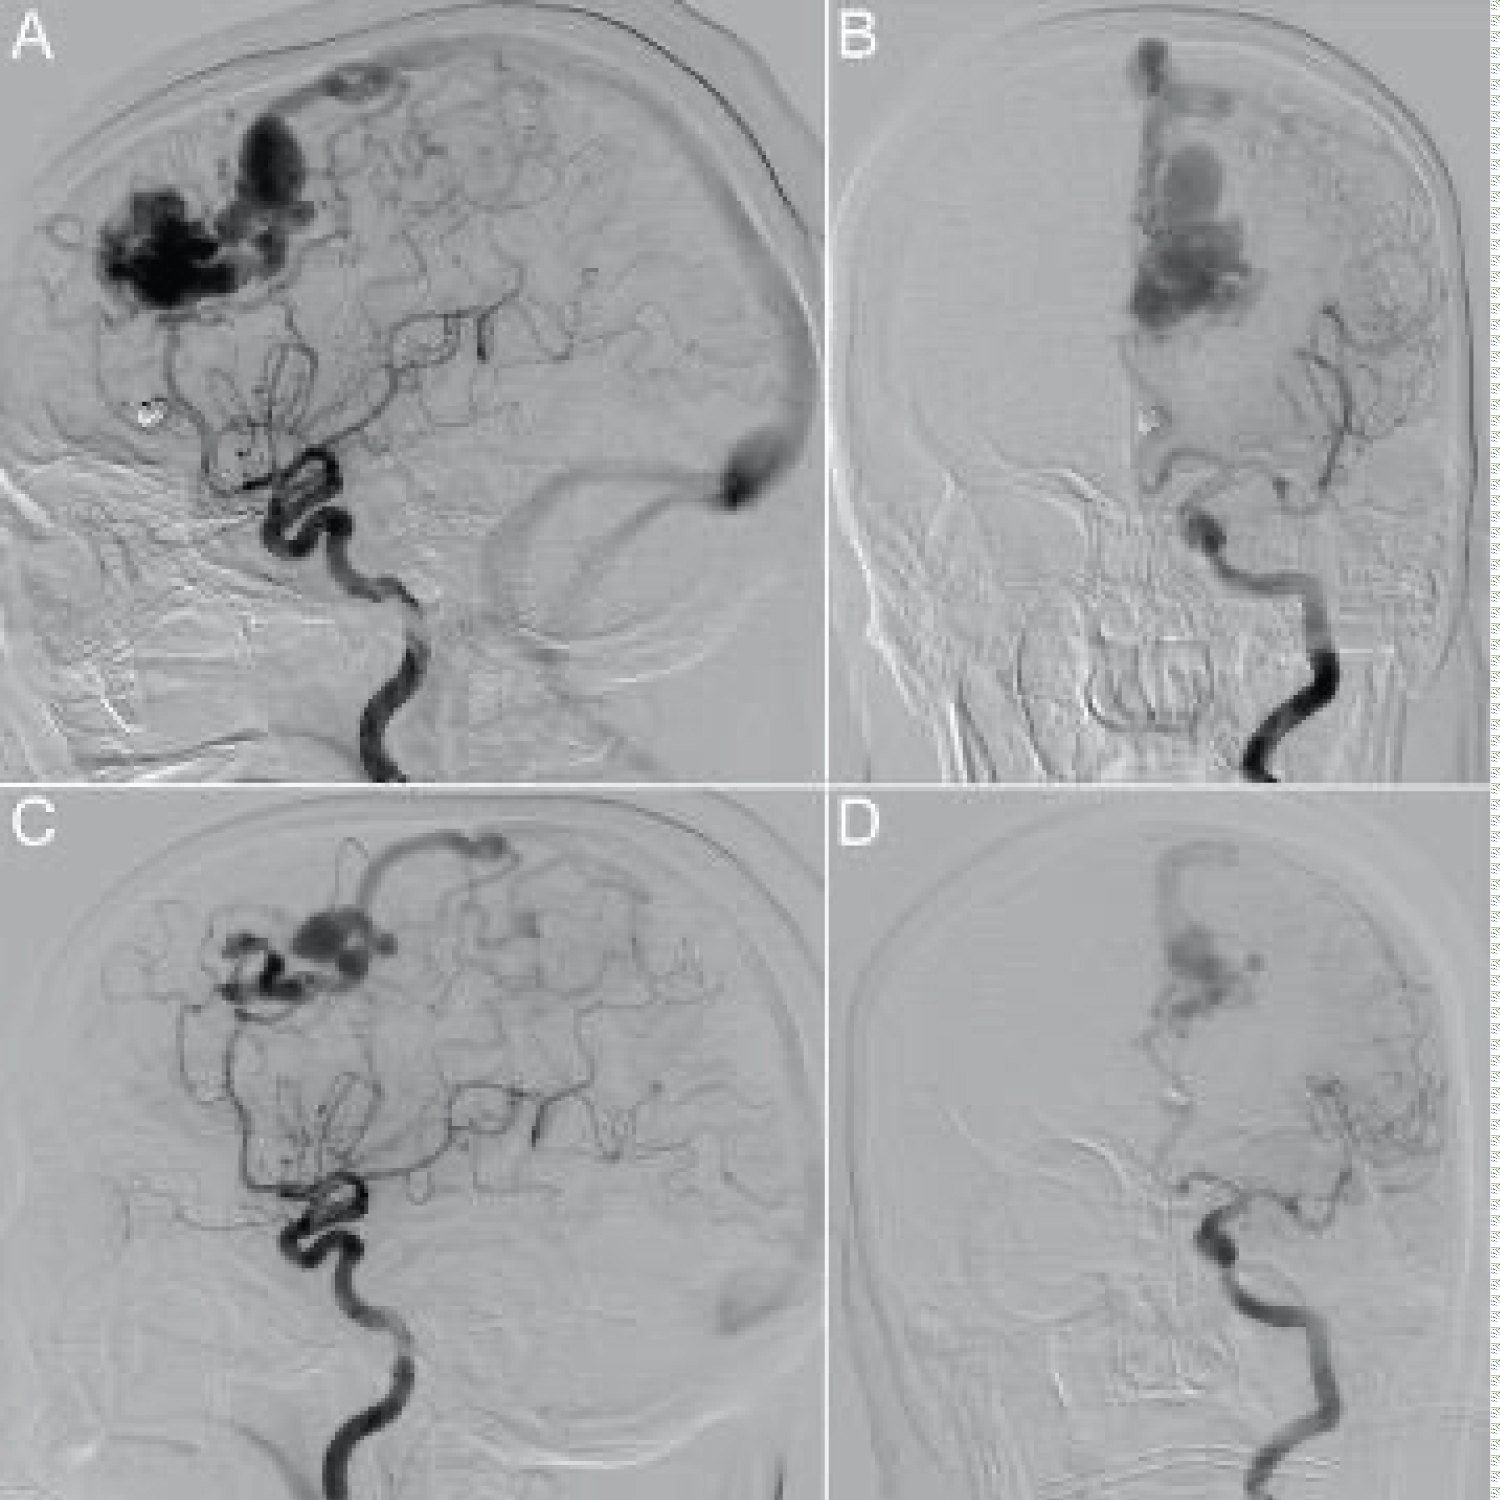

The patient's left frontal lobe AVM was first identified in 2007 with a nidus measuring approximately 21 × 20 × 21 mm. Arterial supply was predominantly from small arterial branches arising the pericallosal and callosomarginal branches of the left anterior cerebral artery. A large tortuous vein provided superficial drainage into the superior sagittal sinus. On follow up imaging, computed tomography angiography (CTA) demonstrated an interval decrease in contrast enhancement within the venous varix (Figure 1). Magnetic resonance imaging (MRI) findings were also suggestive of partial thrombosis within this venous varix and demonstrated an interval increase in vasogenic perivenous edema within the left superior frontal lobe (Figure 2). Four months later the patient underwent digital subtraction angiography (DSA), which revealed a significant decrease in nidus size, suggesting partial thrombosis of the nidus in addition to draining vein thrombosis (Figure 3). Notably, the large ectatic cortical vein draining the residual nidus was now seen to empty into multiple convexity cortical veins, whereas it had previously drained predominantly into the superior sagittal sinus, again suggestive of interval thrombosis of the draining vein.

Figure 3: Left internal carotid artery injection in November of 2017 (lateral projection [A], anterior-posterior projection [B]) and in October of 2020 (lateral projection [C], anterior-posterior projection [D]). The nidus is fed predominantly by a branch of the left pericallosal artery with minor contributions from the left callosomarginal artery. In A and B, drainage into the superior sagittal sinus is via a large tortuous vein with an associated venous pouch. In C and D, there is significant reduction in the size of the AVM nidus. The residual nidus drains via a large posterior cortical vein which subsequently drains into multiple left cerebral convexity cortical veins. The draining vein's multiple ectatic segments have slightly changed in shape and anatomy compared to the previous study. View Figure 3